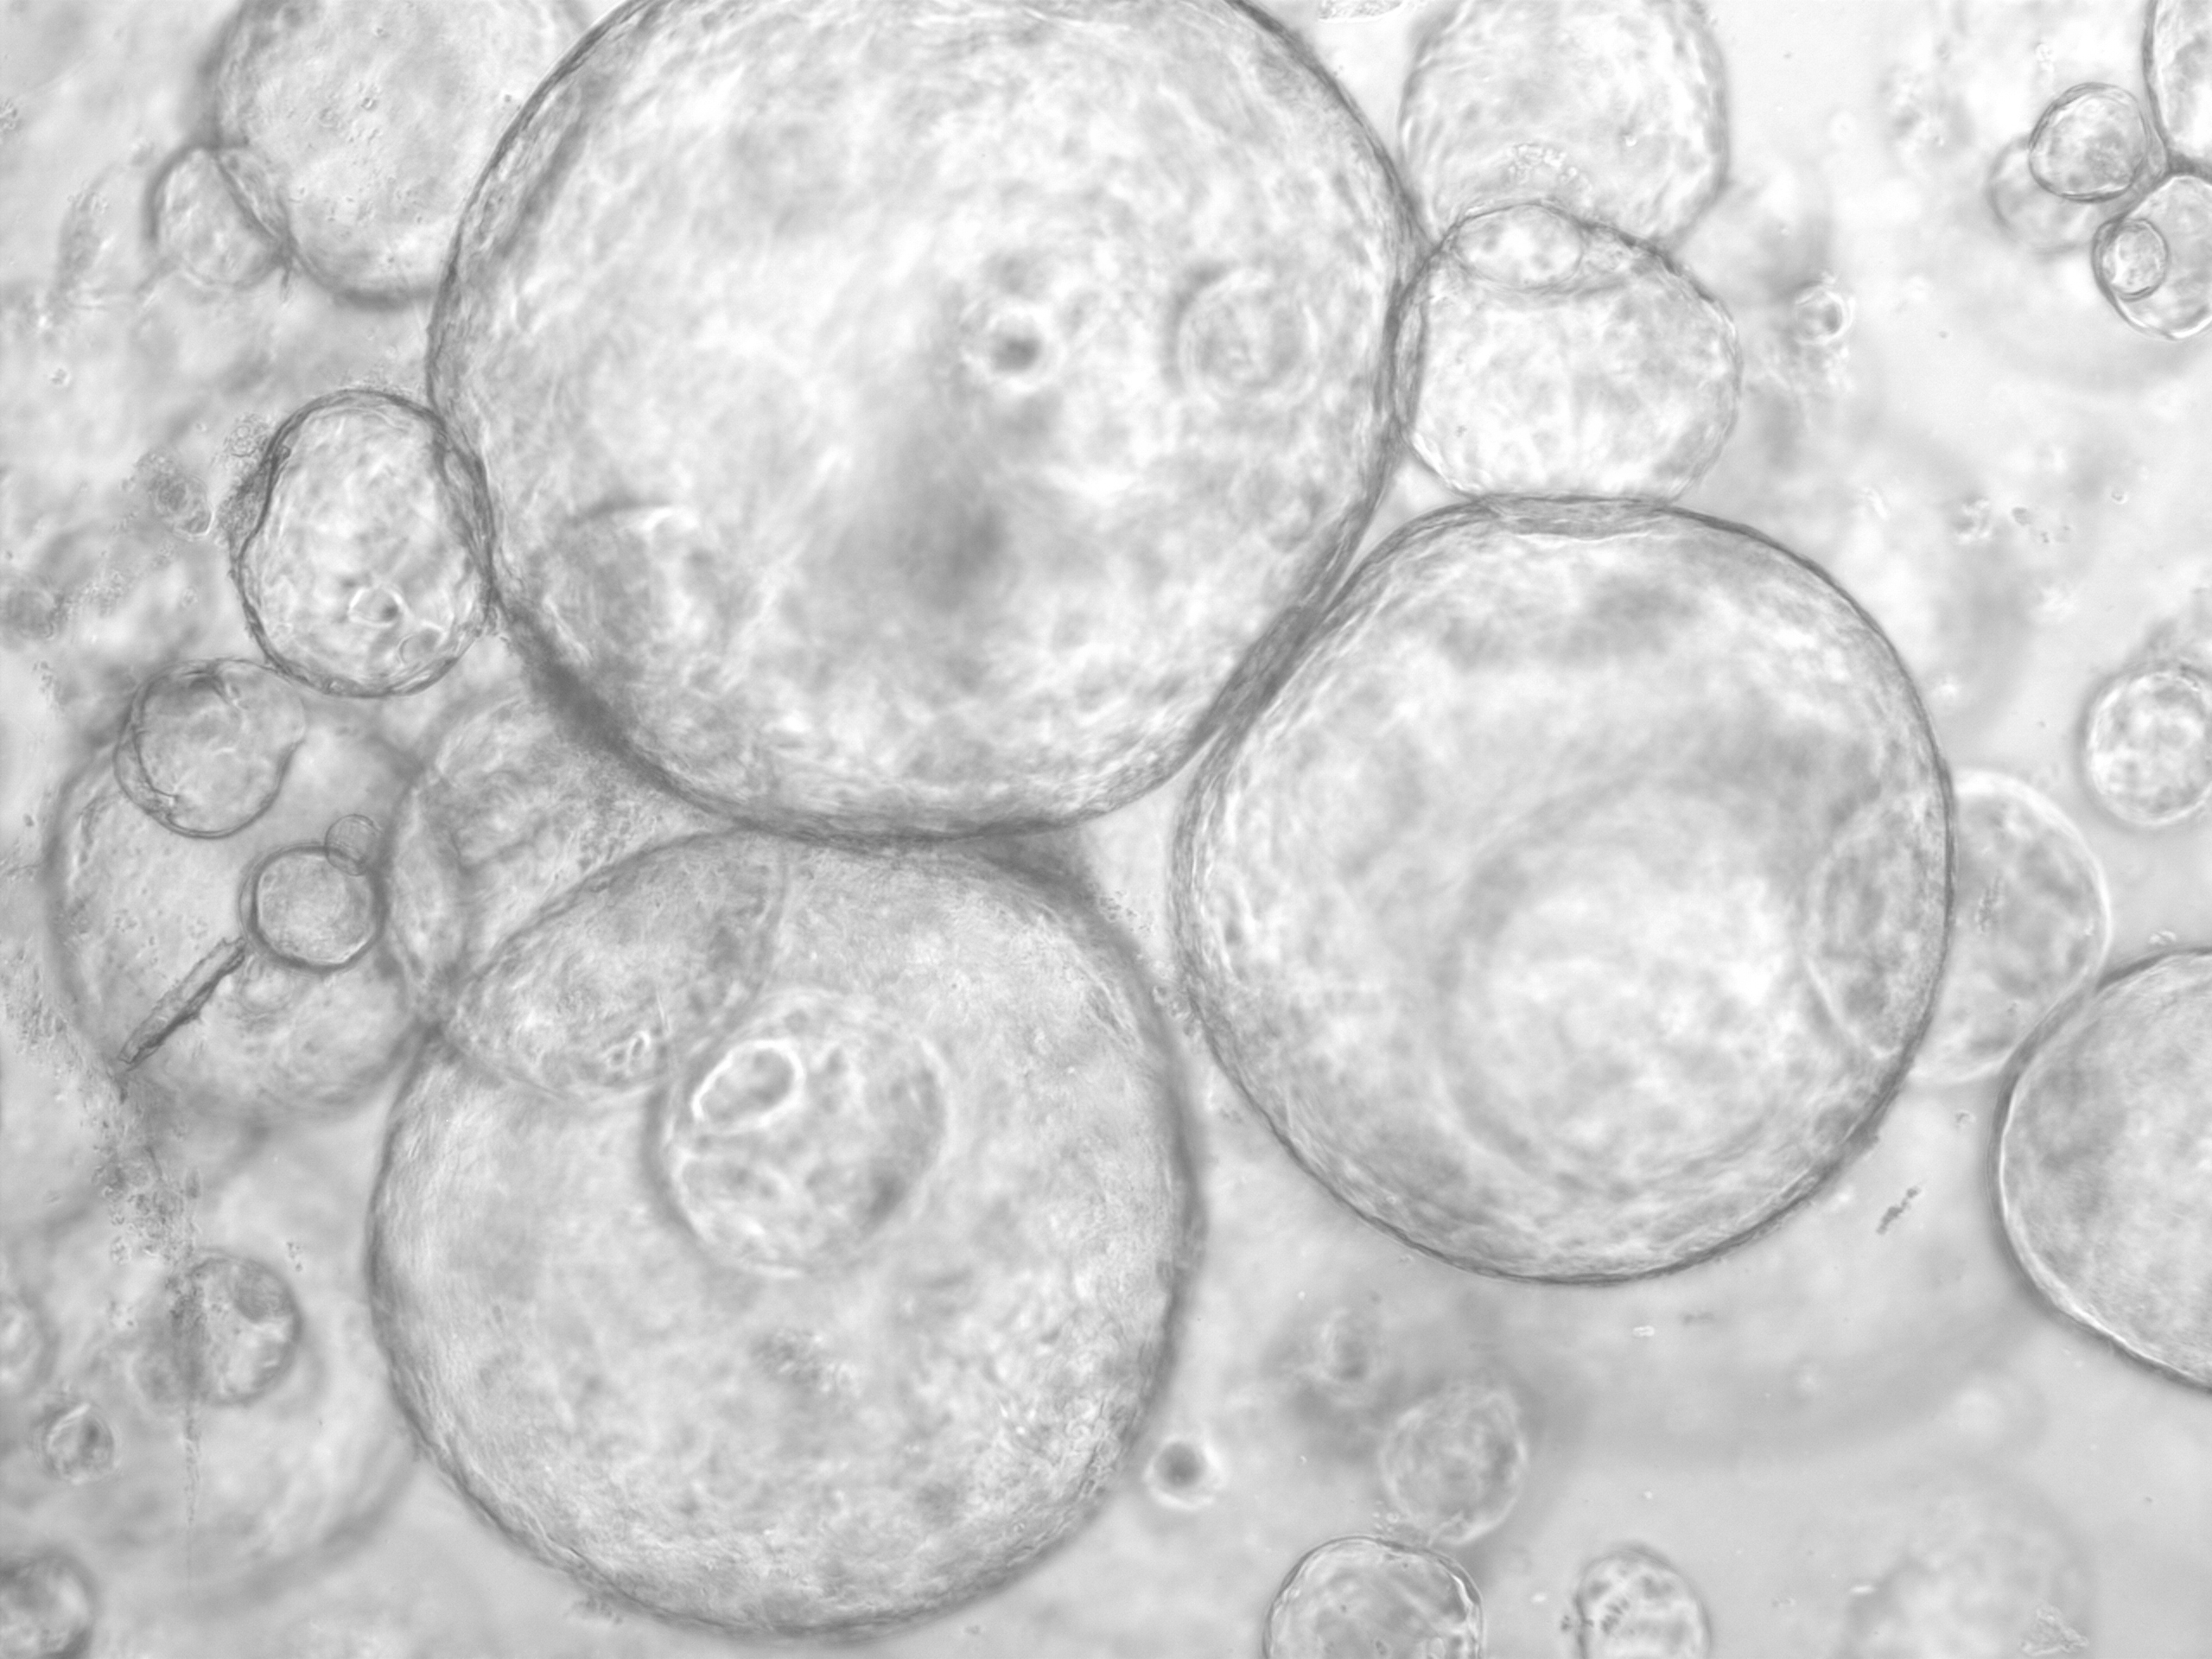

Die Mikroskop-Aufnahme zeigt sogenannte Organoide. Das sind Zellen, die in einer Matrix eine beerenförmige Struktur ausbilden, typischerweise mit einem Hohlraum in der Mitte sowie inneren und äußeren Zellen. Organoide werden für das Projekt aus Gewebeproben von Patient:innen gezüchtet. Auf diese Weise können zum Beispiel Wirkstoff-Wirkungen und die Entstehung von Tumoren untersucht werden.